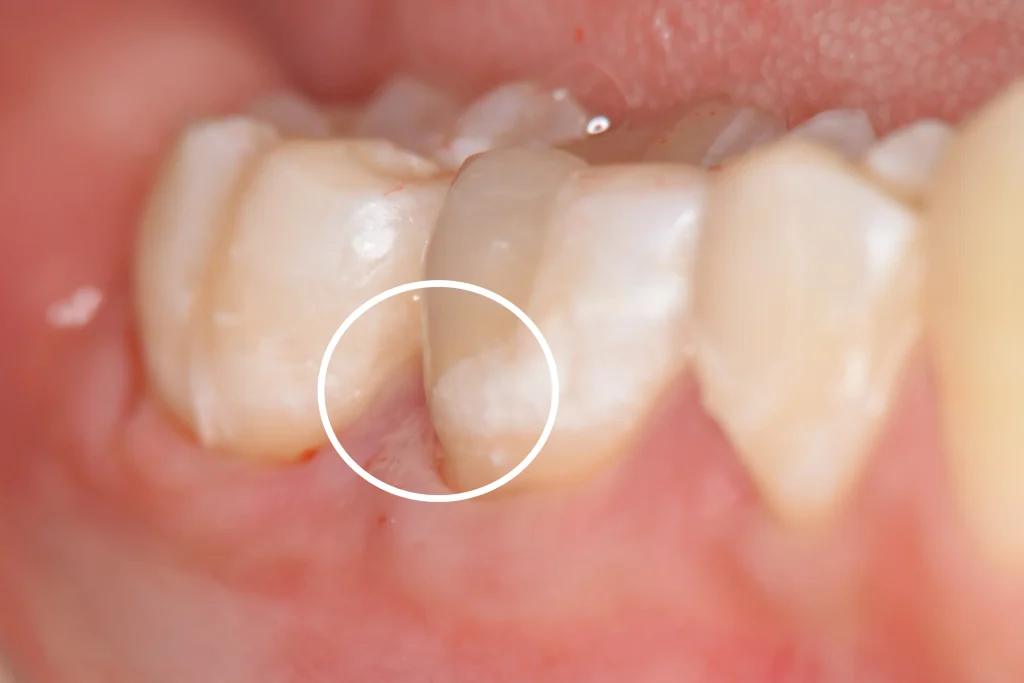

ラバーダム防湿下でセラミックオーバーレイ(テーブルトップベニヤ)を接着しました。

白丸の範囲、隙間が全くないことがわかります。

隙間を作らないことで汚れや細菌が入るスペースを与えず、虫歯の再発予防に寄与すると考えられます。